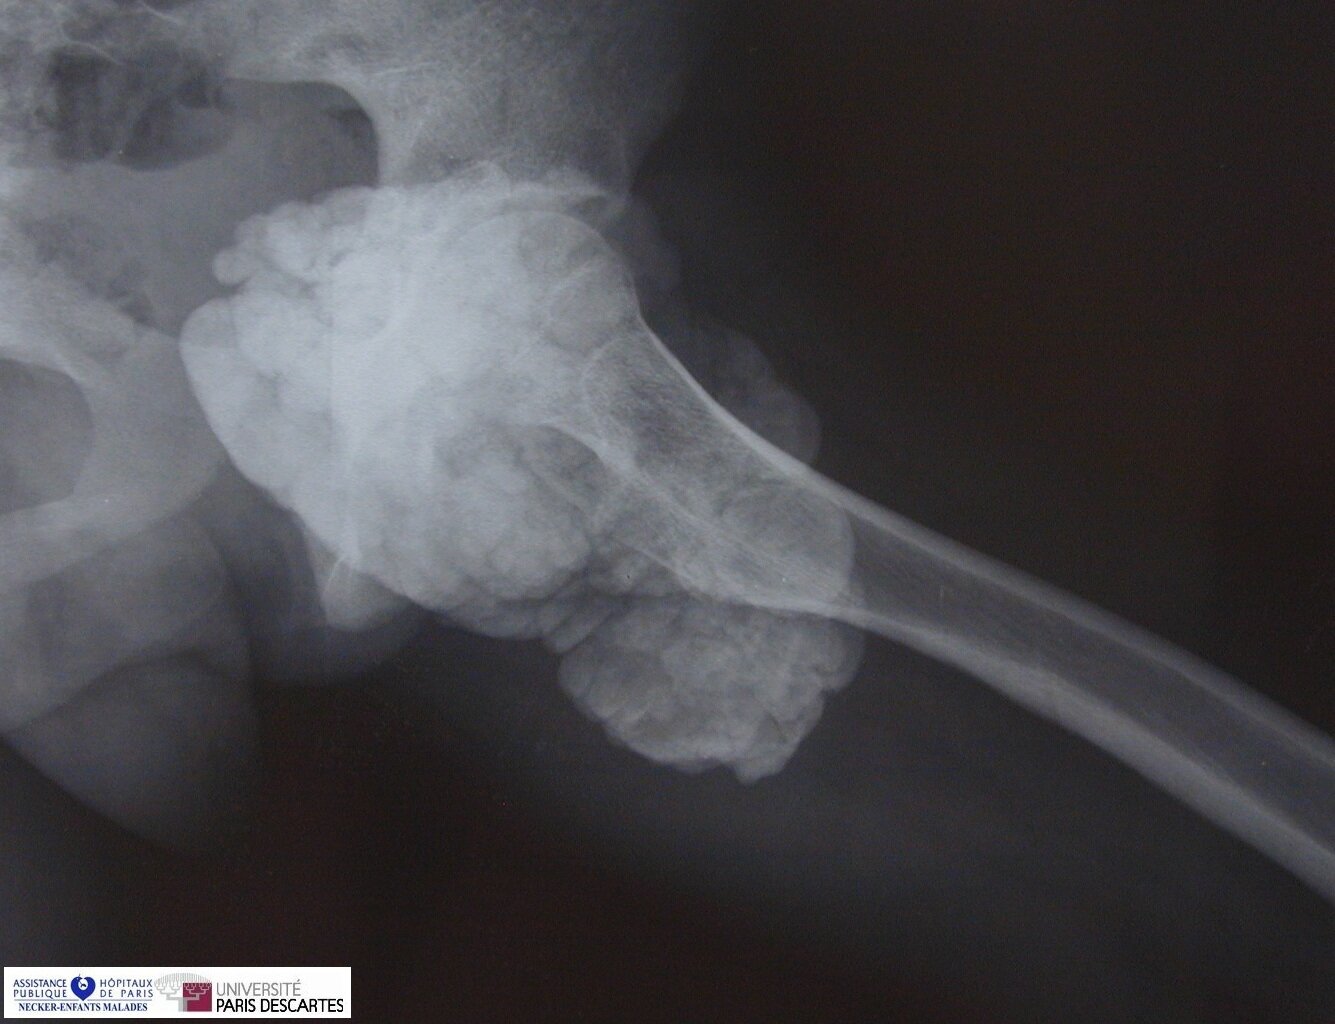

Tumoral Calcinosis